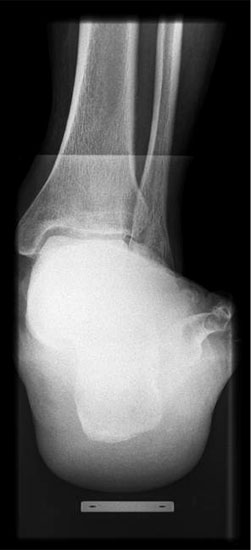

Abbildung Nr. 1: Röntgen Fuß: dp und seitlich stehend.

Abbildung Nr. 2: Saltzmannaufnahme zur Bestimmung des Fersenvalgus.